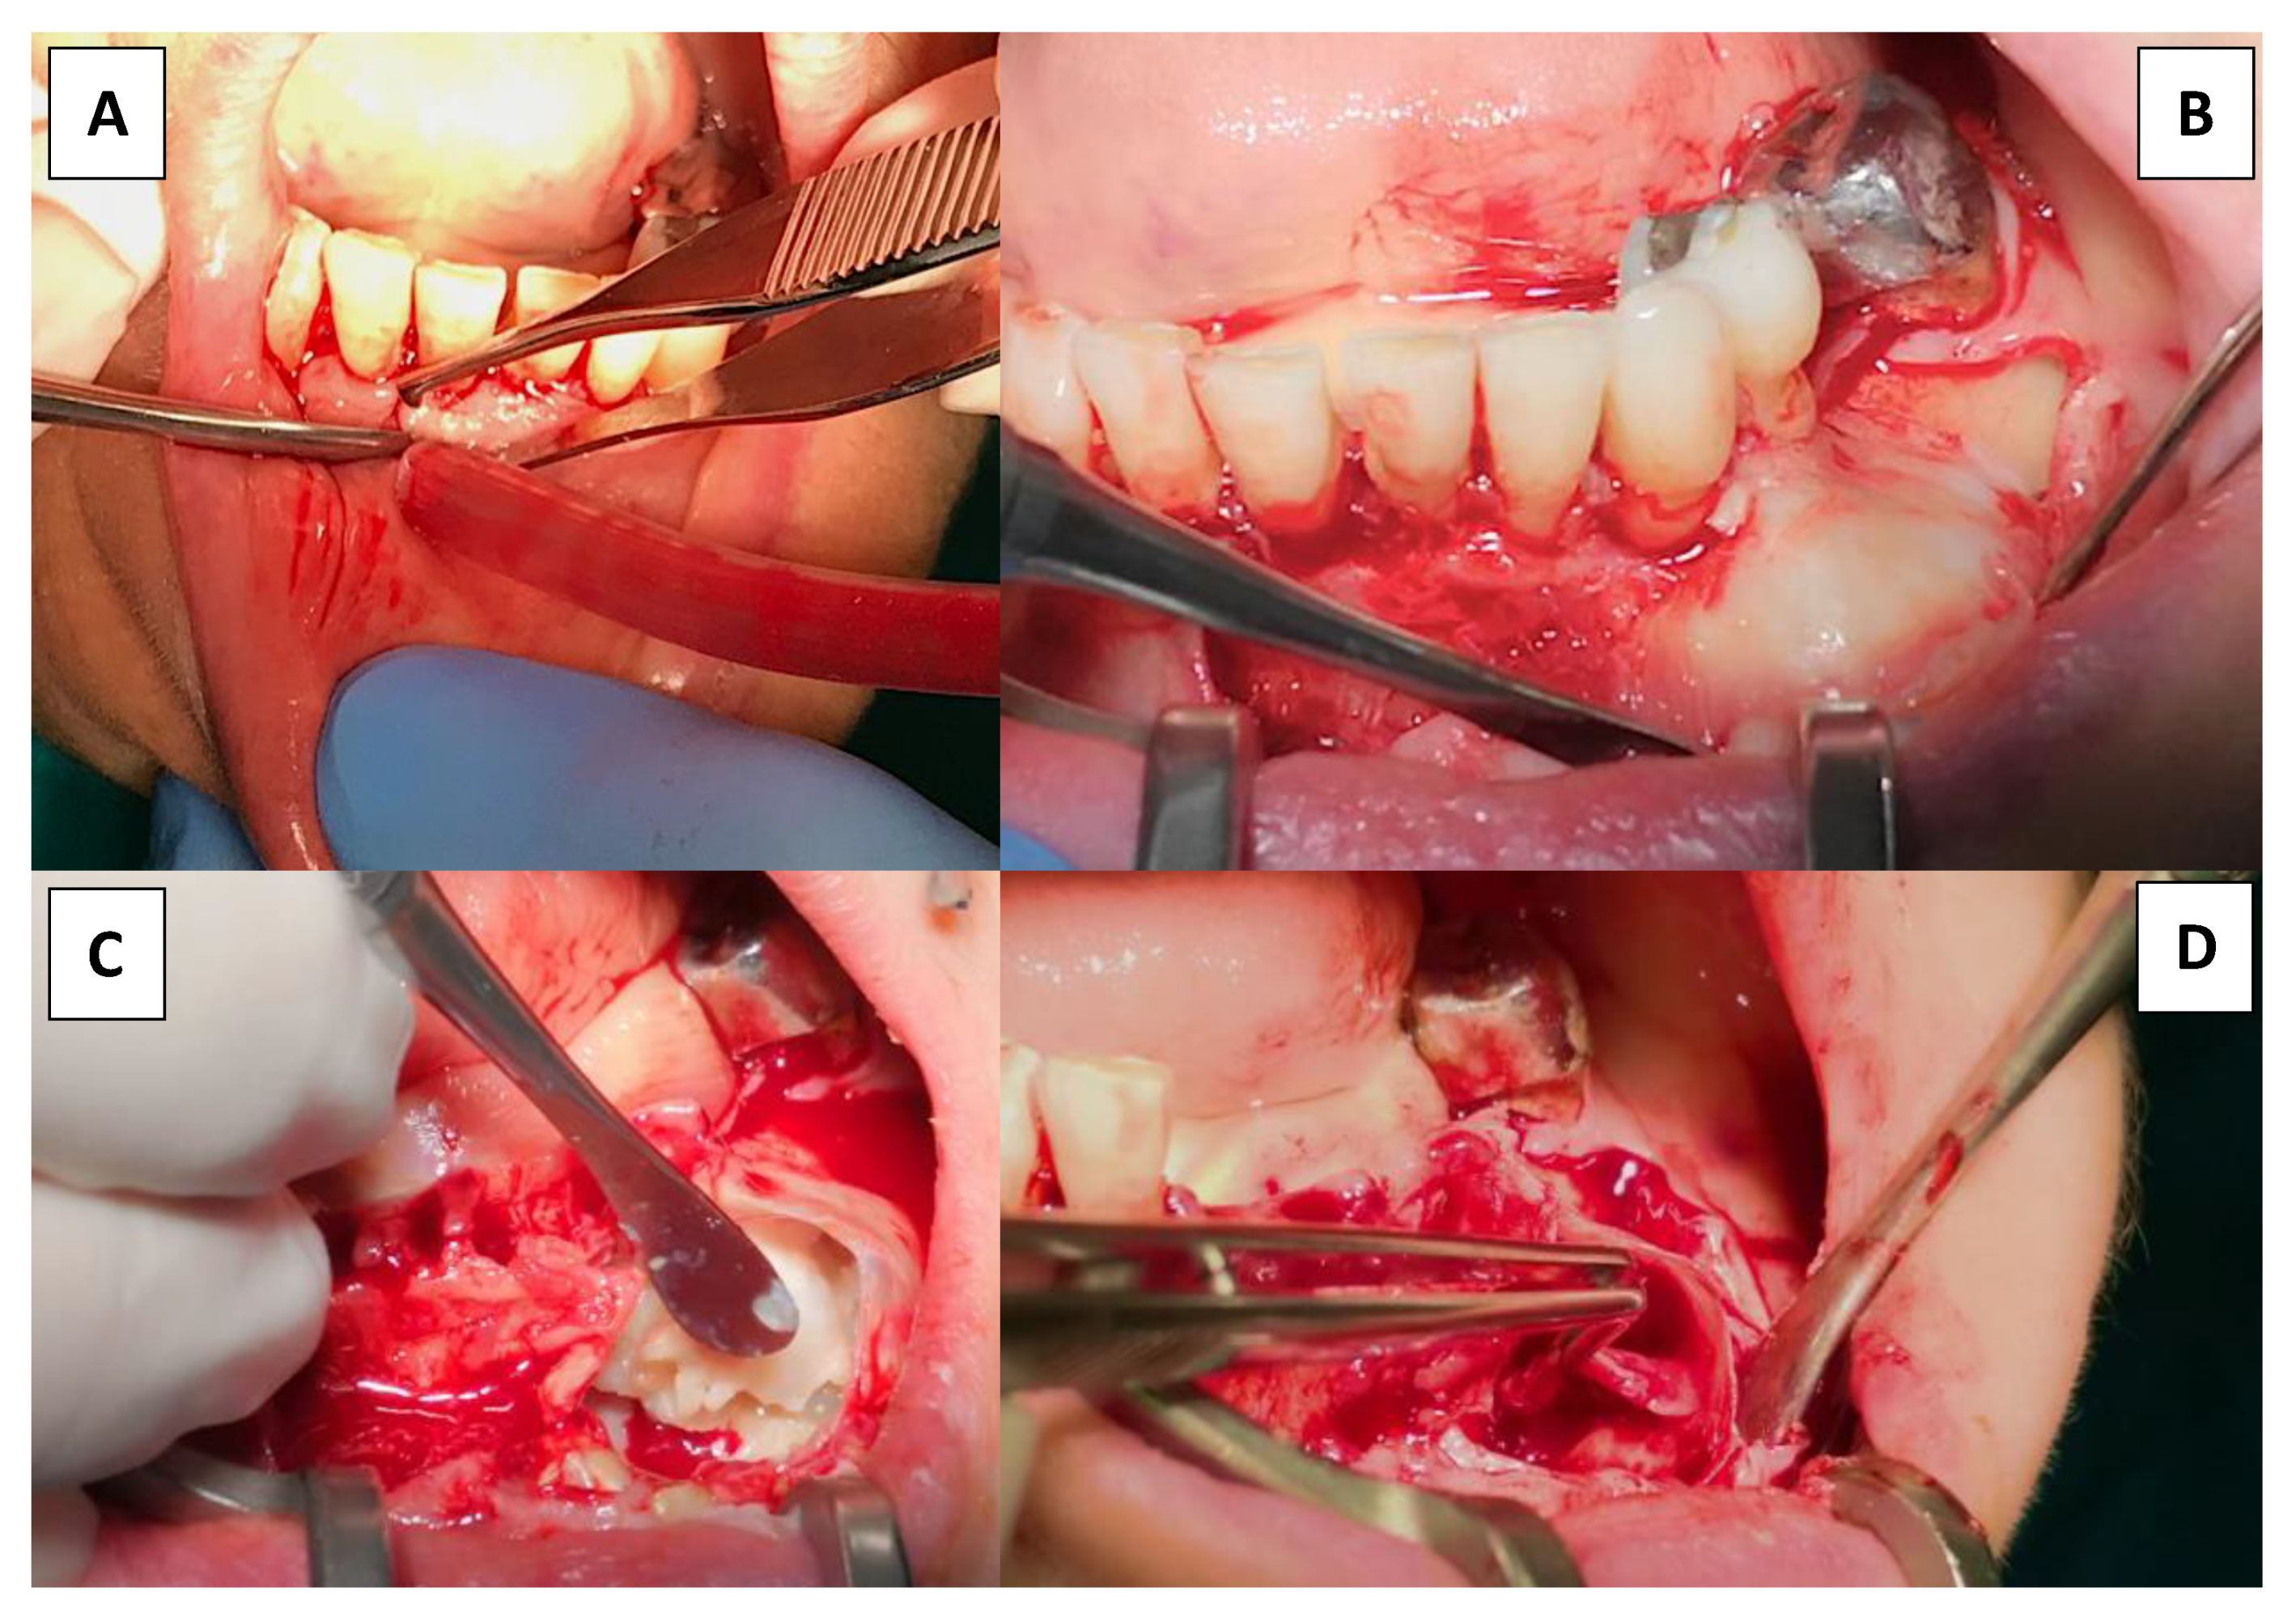

2. Materials and Methods

3. Results